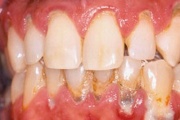

Krooniline parodontiit

Krooniline parodontiit on mikroobide poolt põhjustatud hammaste tugikudede põletik, mille tulemusena tekib progresseeruv alveolaarluu (nähtav röntgenograamil) ja periodontaalligamendi destruktsioon, igemetaskute moodustumine, igeme retsessioon või mõlemad kahjustused kombineeritult. Loe edasi »

Sümptomid:

- igemed veritsevad (19)

- igemed punetavad (21)

- ige on paistes (mädapunn)

- igemed on tursunud/vohavad (17)

- igemed on valulikud (19)

- igemepiir on taandunud (3)

- puudulik suuhügieen (5)

- igemepealne hambakivi (5)

- igemealune hambakivi (4)

- halb hingeõhk / suu haiseb (12)